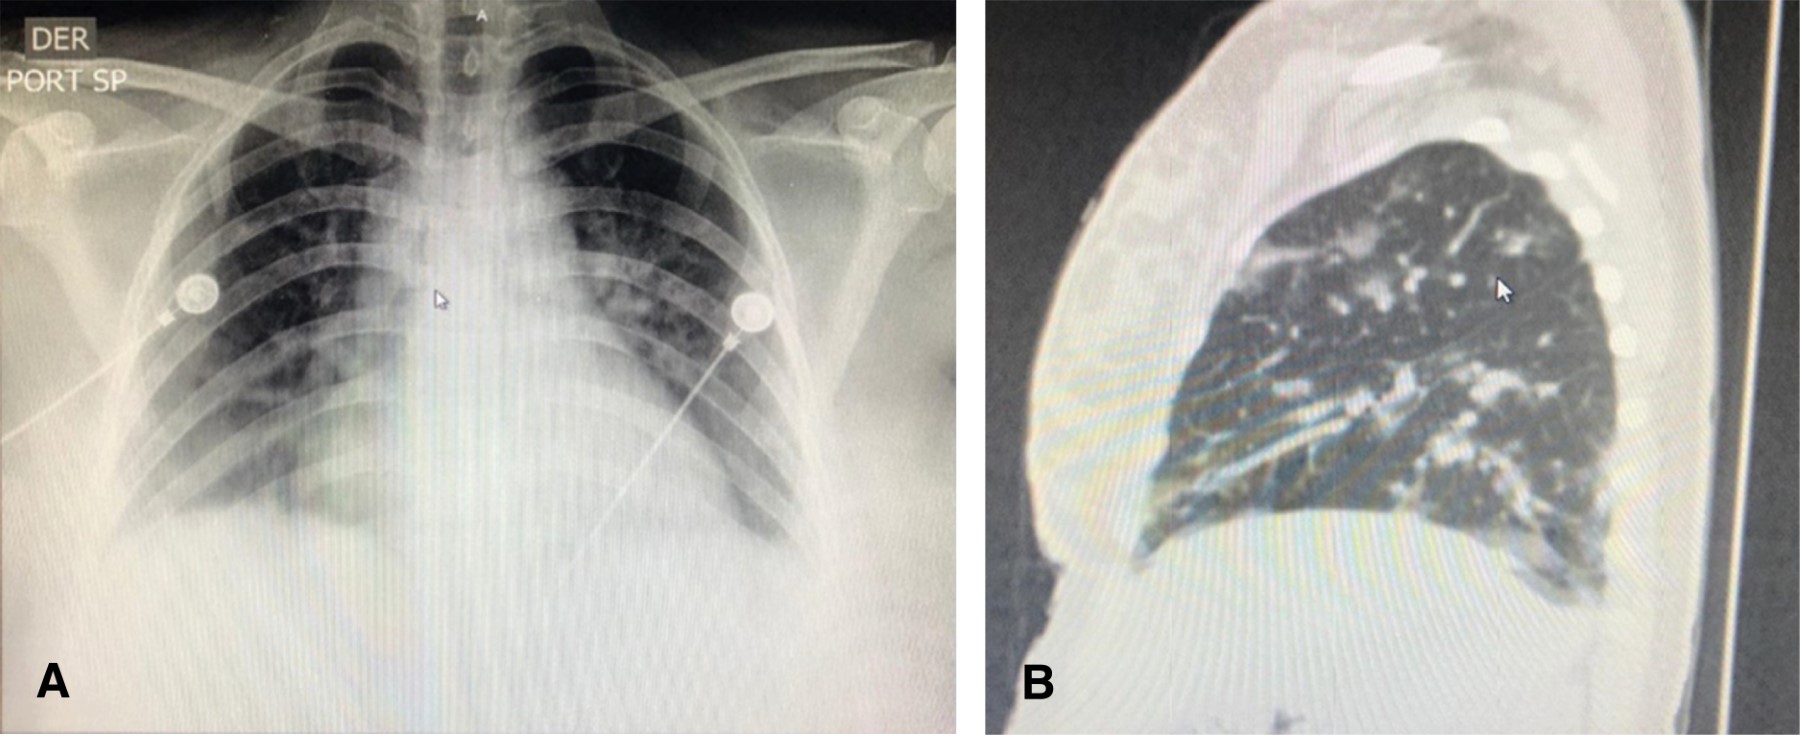

Figure 1